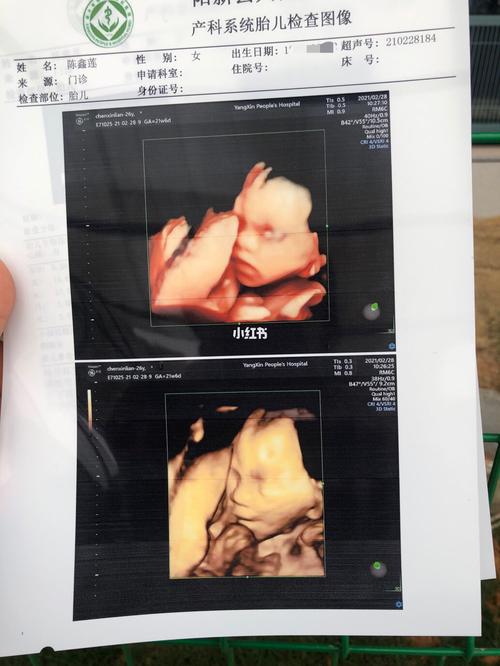

孕21周776 四维彩超_四维彩超_女宝_四维猜男女_母婴_孕产经验

四维彩超已过所以症状女宝太开心

女宝宝四维图片

女宝的四维图

四维彩超女孩清晰图

女孩的彩超图片大全

四维女宝宝器官图片